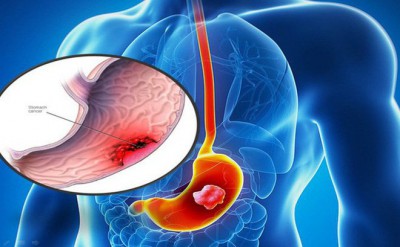

Hiệu quả của hóa trị bổ trợ trong điều trị ung thư dạ dày

Hiệu quả của hóa trị bổ trợ sau phẫu thuật cắt bỏ dạ dày triệt căn ở bệnh nhân ung thư dạ dày ngày càng rõ ràng, mặc dù không có sự đồng thuận để ra một phương thức tiếp cận tốt...